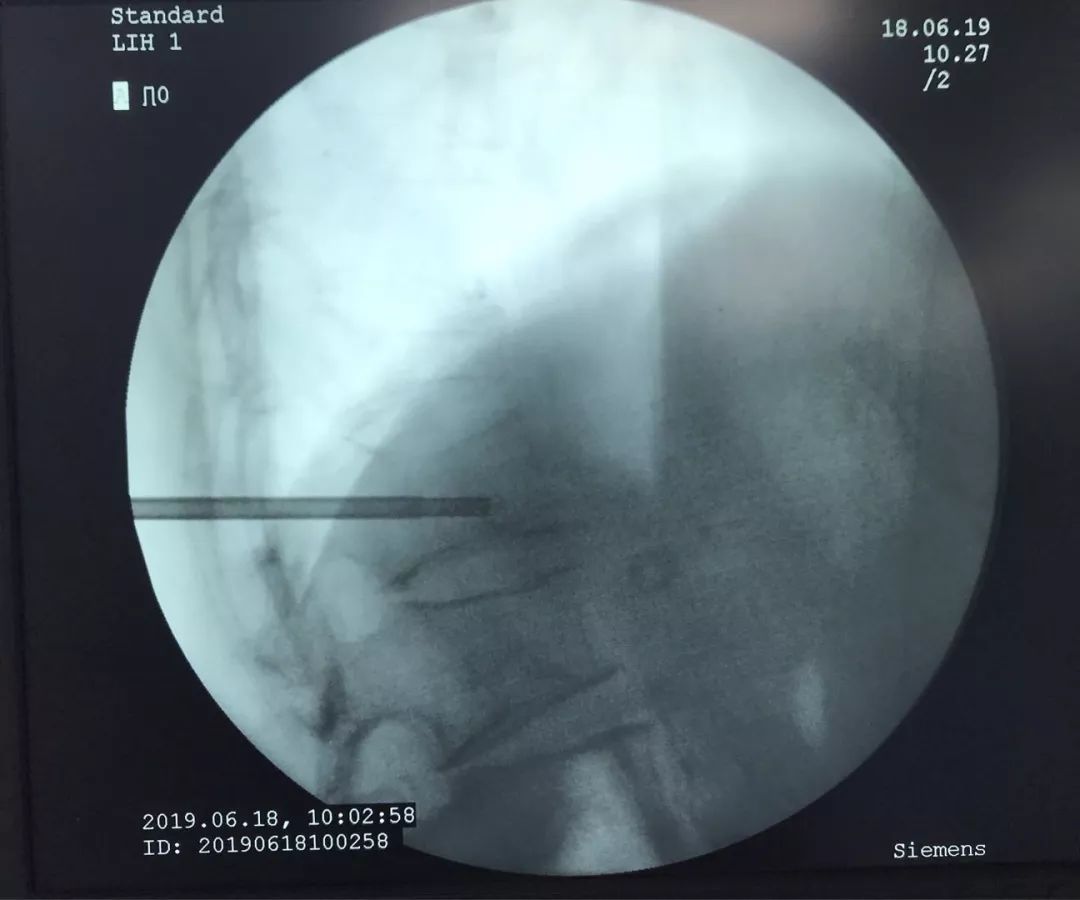

骨水泥灌注术中

灌注骨水泥既可以起到椎体成型的作用,还可以起到止痛的作用。如果是椎体肿瘤,还可以对肿瘤细胞起到杀灭的作用。